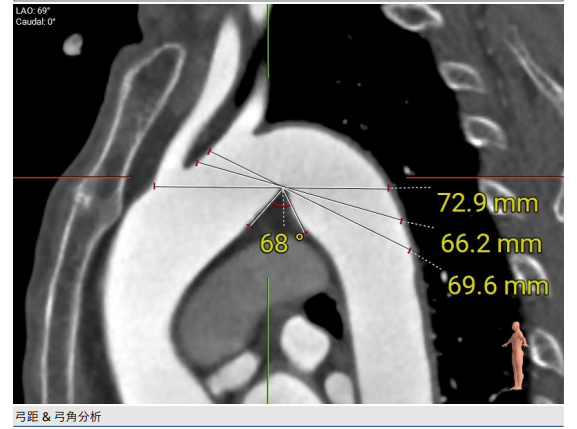

3.血管入路偏细,弓角为锐角,最窄弓距低于70mm。

CT评估

1.瓣环及左室流出道。

2.主动脉瓣根部(左右瓣叶长度均超过冠脉高度)。

3.主动脉弓分析及瓣叶长度(最短弓距小于70mm)。

4.外周血管入路